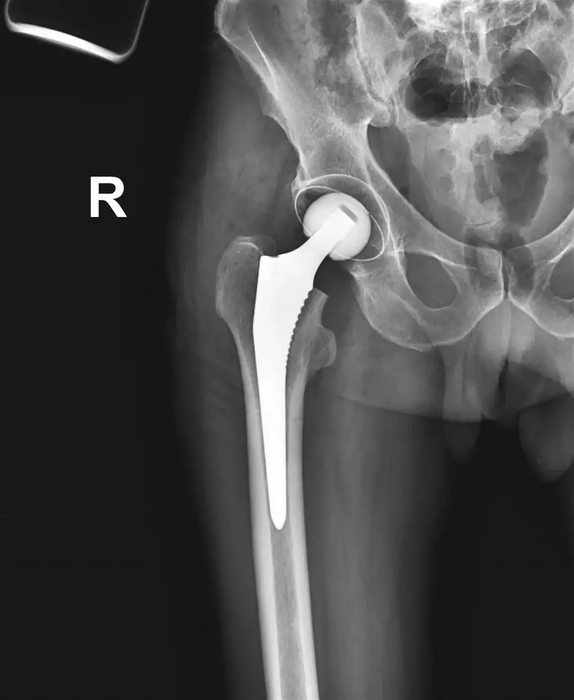

Эндопротез тазобедренного сустава